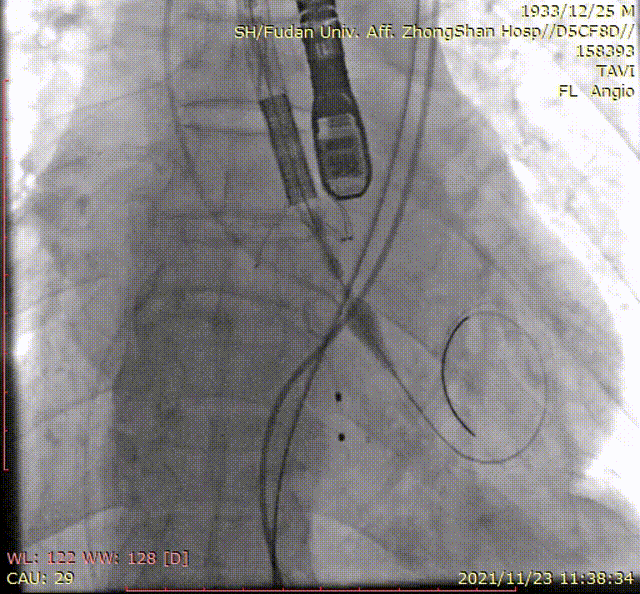

入路解剖

手术过程

输送系统到位